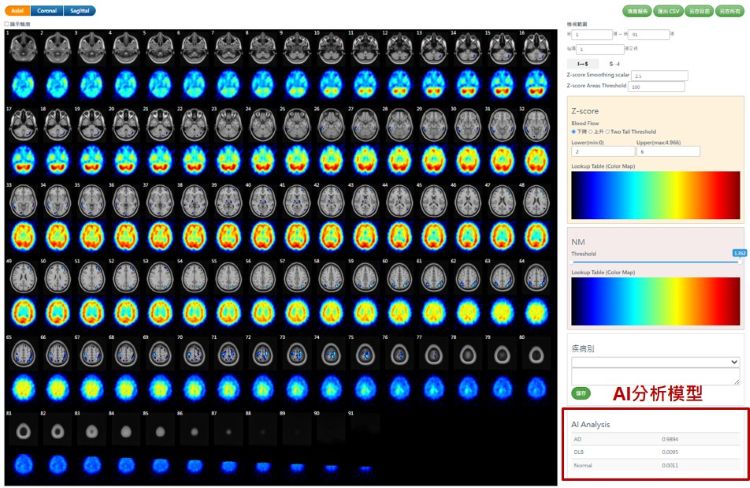

國原院近年積極投入智慧醫療領域研發,成功開發腦血流影像異常分析軟體「ECDaim」,可運用於核醫腦部影像判讀,協助臨床醫師偵測腦部退化性疾病。該軟體以院內自建的腦功能常模資料庫為基礎,透過相對腦血流分析與比對,自動突顯細微的異常區域,顯著提升影像解讀的效率與準確度。

核醫科功能性分子影像能反映失智症病程早期的細微生理變化,是這套智慧判讀系統的核心。核子醫學科主任汪姍瑩醫師分享,AI系統可在資料導入後快速生成半定量Z-score分析報告與三維定位圖,輔助臨床醫師精準辨識腦區血流異常。臨床驗證結果顯示,AI判讀與專家結果一致性高達九成以上,證明人工智慧已成功融入診斷流程。